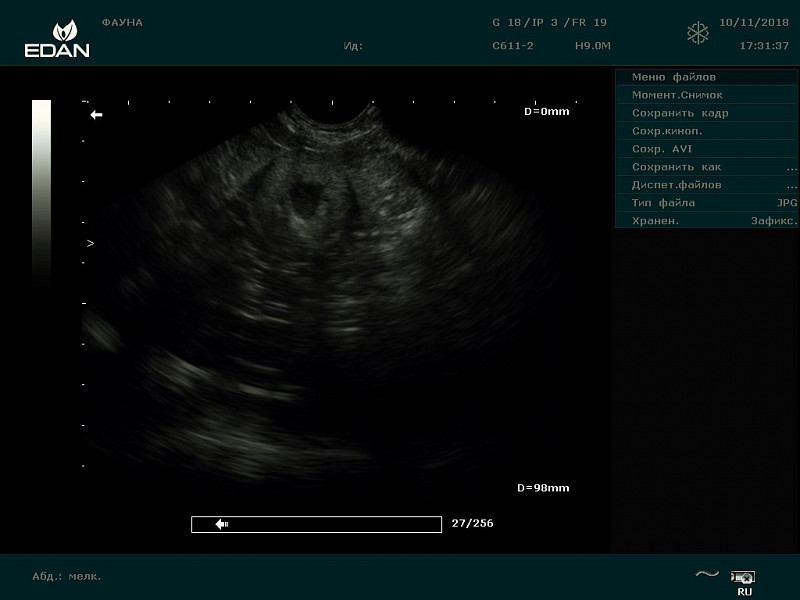

Через неделю сделали УЗИ почек:

Правая: корковый слой - 7,5 мм, мозговой слой - 10,2 мм. Р-ры: длина - 28,8 мм, высота - 26 мм.

Левая: корковый слой - 5,57 мм, мозговой слой - 9,61 мм. Р-ры: длина - 30 мм, высота - 19,8 мм.